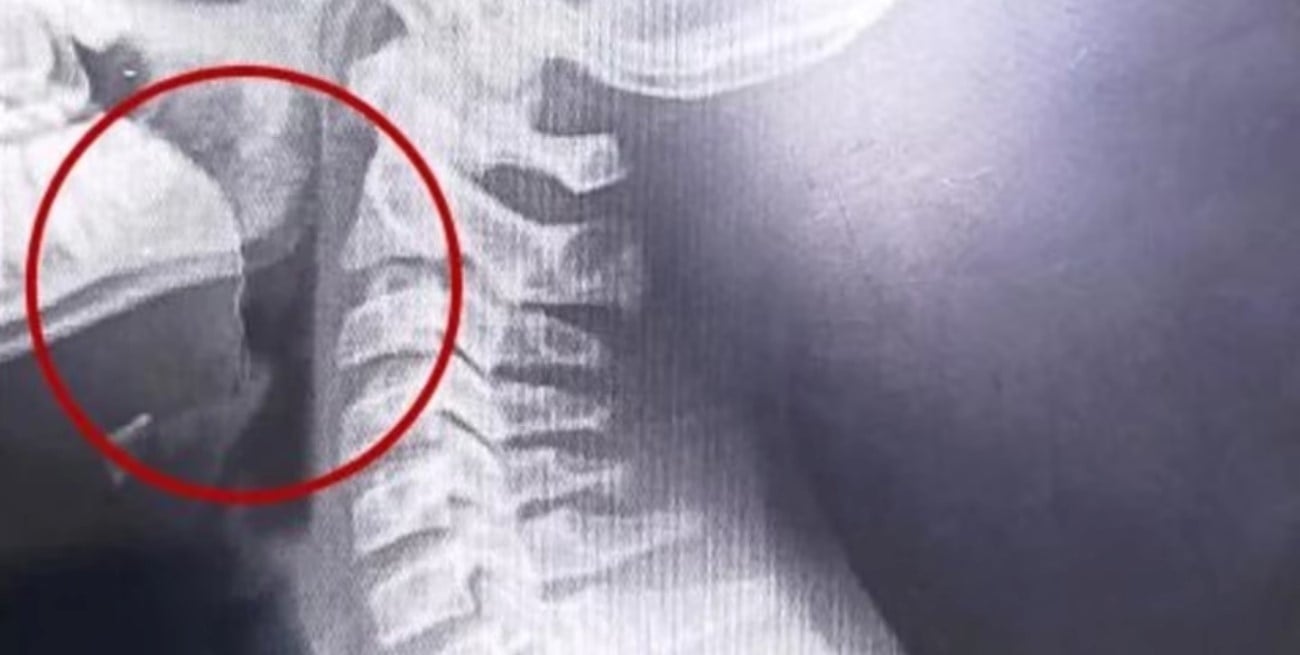

Una vez en el hospital, el enfoque médico cambió. El adolescente fue evaluado de inmediato, internado y sometido a una serie de estudios para determinar el origen del cuadro. Los primeros análisis descartaron infecciones o causas bacterianas, pero la clave apareció con estudios por imágenes.

Las placas revelaron la presencia de un objeto extraño en la vía aérea superior. A partir de ese hallazgo, el equipo médico decidió avanzar con una laringoscopía, un procedimiento que permitió observar directamente la zona afectada.

Durante la intervención, los especialistas detectaron un elemento inusual: un alambre fino que se encontraba incrustado en la garganta del adolescente. Este objeto habría sido ingerido accidentalmente junto con la galletita, provocando las lesiones internas, el sangrado y la dificultad respiratoria.